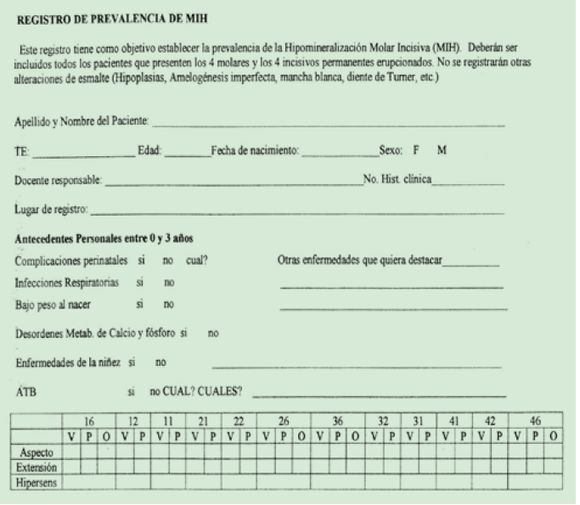

Recolección de datos: El exámen clínico fue visual y se realizó luego de profilaxis, aislación relativa, secado con aire comprimido por 5’’ e iluminación de foco. El instrumento utilizado para la indagación de antecedentes a padre, madre o responsable del niño, fue una entrevista semiestructurada, también denominada semidirectiva, que permitió al entrevistado abordar el tema con libertad y extenderse en torno al mismo. Las entrevistas fueron efectuadas por los tres odontopediatras entrenados y en los contextos naturales de asistencia (clínica de Facultad y consultorio particular).

La guía o estructura básica de preguntas, elaborada previamente, posibilitó analizar la misma información en todos los casos. También se interrogó al niño sobre la presencia de sensibilidad dentaria. Para asegurar la validación del guión seguimos los criterios de confiabilidad planteados por Valles (1997)(12): credibilidad (veracidad de datos) y transferibilidad (posibilidad de referir los datos a otros grupos).

El registro de los datos de sexo, año de nacimiento, lugar de asistencia y presencia de MIH se realizó en planillas diseñadas para tal fin (Fig. 4).

Estandarización de criterios de diagnóstico: Tres especialistas en Odontopediatría, docentes de la Cátedra de Odontopediatría de la Facultad de Odontología, UdelaR, llevaron a cabo un proceso de calibración para el registro de MIH cumpliendo tres etapas: a) homogenización de criterios teóricos, b) observación y discusión de esos criterios sobre fotografías y c) determinación de la concordancia entre los evaluadores a través de la confección de un archivo power-point por un docente externo designado Gold Standard. Se utilizaron 30 imágenes correspondientes a 106 piezas dentarias para evaluar la variación en el diagnóstico visual de un observador respecto de sí mismo (a través de la presentación de las mismas imágenes en diferente posición y forma), y entre los examinadores del grupo de trabajo. El proceso fue repetido a los 15 días. La concordancia en el diagnóstico fue determinada a través del coeficiente Kappa cuyo resultado fue: intra 100% e inter 0.99, 0.98 y 0.90.

Para mantener la concordancia a lo largo del proceso de recolección de los datos, aquellos casos que ofrecían dificultad en el diagnóstico fueron evaluados por dos de los examinadores en forma independiente y luego se confrontaron los resultados para lograr el acuerdo.

Se clasificó la severidad de las lesiones por MIH según su aspecto: de color blanco crema, amarillo marrón y pérdida de esmalte (Fig. 6).